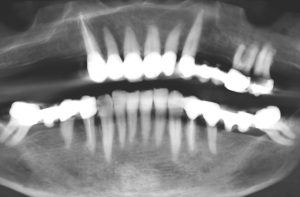

O diagnóstico padrão com escaneamento intraoral e CTCB (Fig. 3 escaner intraoral e Fig. 4 CTCB) mostrou disponibilidade óssea reduzida nas regiões 15 a 17, mas suficiente para a colocação imediata do implante. O dente 13, restaurado endodonticamente, apresentava uma obturação radicular que se estendia claramente além do ápice, juntamente com periodontite periapical. Em consulta com o paciente, foi decidido remover o dente.

A paciente havia recebido anteriormente uma proposta de tratamento de outro dentista, que incluía uma elevação do seio maxilar pela técnica de abertura lateral do seio, com aumento do rebordo lateral alveolar como parte do plano de tratamento da maxila direita. Entretanto, esse plano não atendia ao desejo do paciente de uma restauração fixa minimamente invasiva. Uma restauração protética removível não era uma opção para a paciente. Juntamente com a paciente, definimos a meta de obter uma restauração temporária imediata, embora inicialmente de longo prazo, da função e da estética em um único procedimento minimamente invasivo.

O planejamento digital das posições ideais dos implantes em 3D, tanto do ponto de vista cirúrgico quanto protético, foi realizado usando o software de planejamento de implantes exoplan (exocad), com base em dados escaneados de CTCB e intraorais. O desafio era planejar a colocação imediata do implante na região 13 ao lado de dois implantes adicionais, garantindo a utilização ideal do osso disponível em termos de estabilidade primária suficiente para carga imediata por meio de uma restauração imediata provisória de longo prazo com uma ponte implantossuportada. Um implante (comprimento 10 mm, diâmetro 3,3 mm) foi posicionado exatamente na frente do seio maxilar na região 15 e o segundo implante (comprimento 8 mm, diâmetro 4,1 mm) foi planejado na região 17 (Fig. 6). As atenções do software e as indicações de distância de segurança foram particularmente úteis nesse processo.